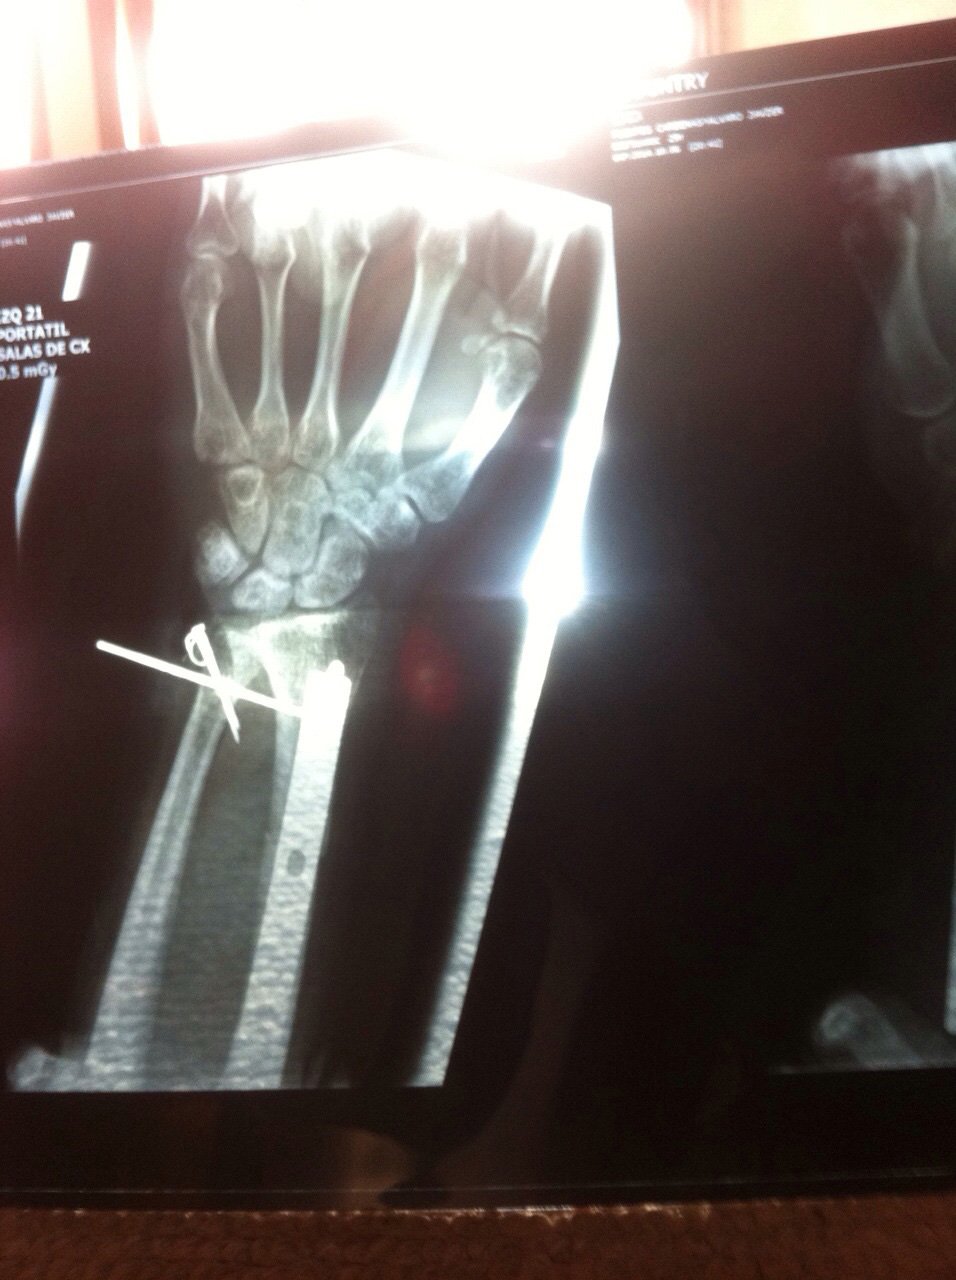

It’s 2014, and I’ve just come through what I half-jokingly called my early-thirties crisis — a rough stretch filled with frustration, physical pain, and big questions about where my life was heading. It was a rough patch marked by a broken arm, three surgeries, and eleven screws, two plates, and one rod now holding my forearm and wrist together. Back then, I was starting to consider a career change from being an industrial designer to becoming a photographer.

Not knowing what I was going to do, I packed everything I could into my backpack. Everything! I made sure the batteries were charged and off I went, with only one functional arm — the other in a cast, supported by a neck sling. The new camera, the new lens, a bunch of other lenses (mostly cheap ones), a flash, and a lot of excitement and questions. What exactly was I going to shoot? Would it be easy? Surely it was just shooting the performer. I had the whole concert, surely I could get something good.